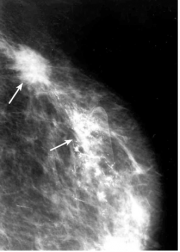

| 16:15, 5 בספטמבר 2012 | Breastcancer2212.png (קובץ) |  |

125 קילו־בייטים | Motyk | 1 | |